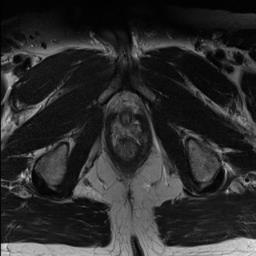

Modern deep neural networks struggle to transfer knowledge and generalize across diverse domains when deployed to real-world applications. Currently, domain generalization (DG) is introduced to learn a universal representation from multiple domains to improve the network generalization ability on unseen domains. However, previous DG methods only focus on the data-level consistency scheme without considering the synergistic regularization among different consistency schemes. In this paper, we present a novel Hierarchical Consistency framework for Domain Generalization (HCDG) by integrating Extrinsic Consistency and Intrinsic Consistency synergistically. Particularly, for the Extrinsic Consistency, we leverage the knowledge across multiple source domains to enforce data-level consistency. To better enhance such consistency, we design a novel Amplitude Gaussian-mixing strategy into Fourier-based data augmentation called DomainUp. For the Intrinsic Consistency, we perform task-level consistency for the same instance under the dual-task scenario. We evaluate the proposed HCDG framework on two medical image segmentation tasks, i.e., optic cup/disc segmentation on fundus images and prostate MRI segmentation. Extensive experimental results manifest the effectiveness and versatility of our HCDG framework.